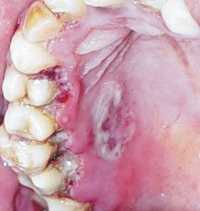

На фото симптомы язвенно-некротического гингивита

Острый гингивит проявляется болью, усиленным слюноотделением, неприятным запахом изо рта. Хронический гингивит проходит медленно, для него характерны кровоточивость, синюшность и разрыхление десен.